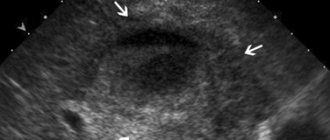

The main instrumental diagnostic method is ultrasound examination (US). Stones or various forms of biliary sludge are detected in the gallbladder and/or common bile duct (Fig. 2, 3, 4). If it is difficult to visualize the common bile or pancreatic duct using transabdominal ultrasonography, endoscopic ultrasound is used (Fig. 5). The common bile duct can be of normal size; its expansion occurs when a stone is pinched in the terminal section or ampulla of the major duodenal papilla. The Wirsung duct is of normal size or moderately dilated. It should be noted that the normal size of the common bile duct according to ultrasound is not a convincing sign of the absence of pathology in it. According to our data (Fig. 6), with a common bile duct width of up to 6 mm, accepted by most researchers as the norm, the frequency of detection of stones in the common bile duct with cholecystolithiasis is 20.6%, and with the gallbladder removed for cholelithiasis - 43.4%. Changes in the pancreatic parenchyma depend on the stage of the process. In the early stages, changes in the pancreas cannot be detected. Subsequently, the heterogeneity of the structure and the unevenness of its contours are revealed. During exacerbation of PD, ultrasound signs of edema of pancreatic tissue are detected. Dynamic cholescintigraphy (DCSG) is indicated to determine the patency of the bile ducts. The ability to trace the entire process of bile redistribution with analysis of its accumulation and evacuation into the duodenum is a valuable advantage of DHSG [6], especially in PD, when ERCP is associated with a high risk of exacerbation of the pathological process in the pancreas. At the same time, ERCP is the most common method for diagnosing pathology of both the biliary system and the pancreas. If necessary, papillotomy or papillosphincterotomy is simultaneously performed during the examination. Violation of the functional state of the pancreas, as mentioned above, is not always accompanied by changes in its parenchyma, therefore methods such as computed tomography, nuclear magnetic resonance and transabdominal ultrasound may be uninformative. An alternative method for diagnosing PD in these cases is EUS. Recently, in clinical practice, magnetic resonance cholangiopancreaticography has been increasingly used to diagnose PD, which allows simultaneous assessment of the condition of the bile and pancreatic ducts. Various criteria have been proposed for predicting the severity of pancreatitis. The most widely used system is based on the Renson criteria [5], which can also be applied to PD.